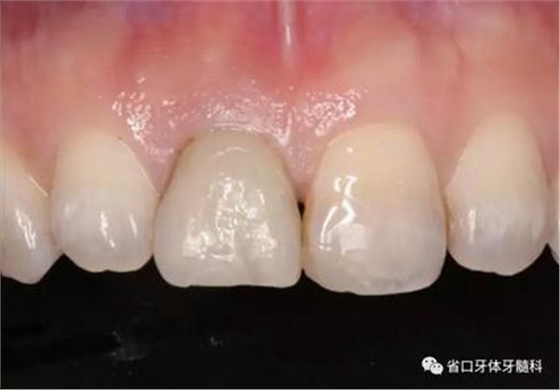

圖1 術(shù)前口內(nèi)照

圖2 術(shù)前口內(nèi)照

圖3 術(shù)前口內(nèi)照

1.?病例簡介 43歲女性患者,主拆:右上前牙松動不適數(shù)日要求修復(fù)。現(xiàn)病史:患者數(shù)年前右上前牙因“齲壞”于外院行根管治療(具體不詳),數(shù)日前牙冠松動不適,現(xiàn)覺影響咀嚼及美觀,遂來我院要求進(jìn)一步診治。否認(rèn)高血壓、心臟病等重大疾病,否認(rèn)結(jié)核、肝炎等傳染病史,否認(rèn)手 術(shù)、輸血史等,未發(fā)現(xiàn)藥物過敏。無吸煙習(xí)慣。臨床檢查:口外觀顏面基 本對稱,皮膚無紅腫破潰,顳下頜關(guān)節(jié)區(qū)無彈響、雜音、壓痛,開口度約 37mm,開口型“↓”,頜下、刻下和頸部未及腫大淋巴結(jié)。中位笑線??趦?nèi)檢查,口腔衛(wèi)生可,色素(+),BOP(-),PD=2mm,上頜右側(cè)中切 牙冠部變色,冠根折斷至齦下3mm,叩不適,松動Ⅱ°~Ⅲ°。牙齦稍紅, 齦緣水平及齦乳頭高度可,屬于中厚齦生物型,附著齦寬度約5mm,唇系帶附著可。上頜右側(cè)中切牙缺牙間隙與對側(cè)同名牙一致,約>7mm,修復(fù)空 間良好。與對頜牙覆合覆蓋正常。MCT檢查示上頜右側(cè)中切牙冠根折斷至骨 下,根管內(nèi)見充填物,根充不全,根尖見陰影,大小約3mm×3mm。牙槽窩根方可用骨量可,唇側(cè)骨壁完整,冠方骨壁厚度約1mm。